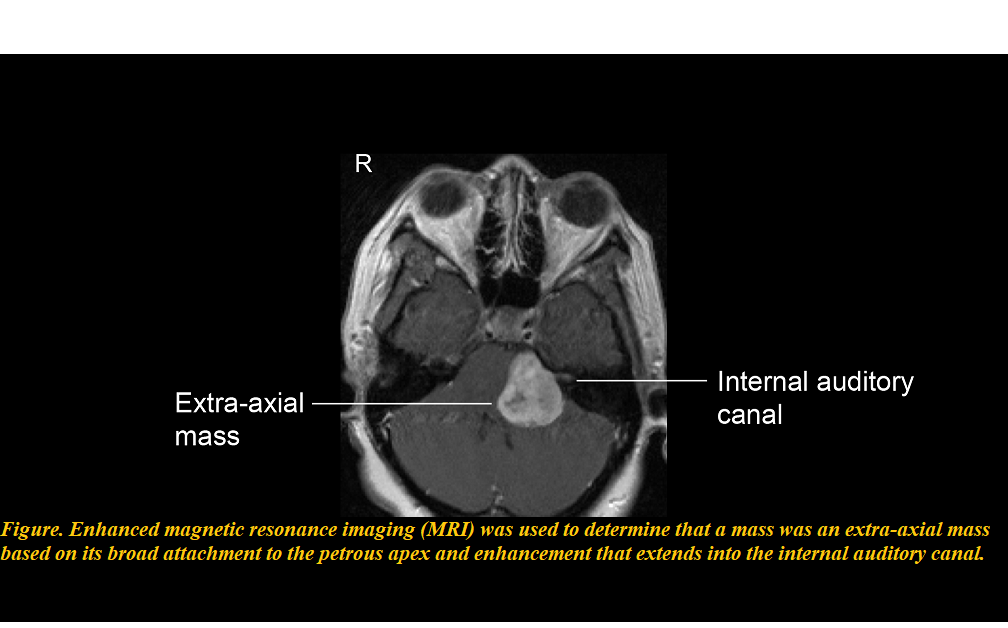

Brain Infection***